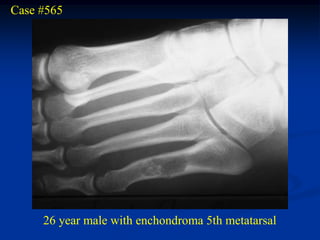

Case #565

26 year male with enchondroma 5th metatarsal